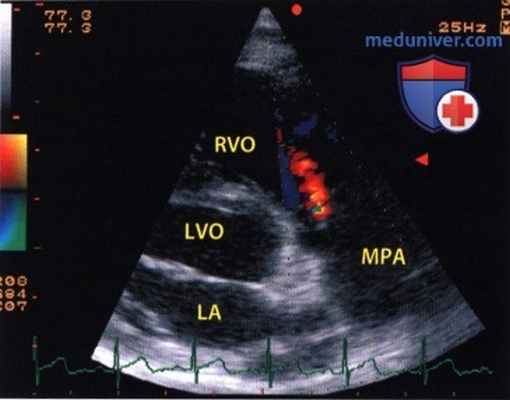

Недостаточность клапана легочной артерии, выявленная при сканировании вдоль оси легочного ствола (МРА) при дуплексном исследовании.

Диастолическая струя регургитации забрасывается в выносящий тракт правого желудочка (RVO), по времени следует за зубцом Р ЭКГ и окрашена в желто-красно-зеленый цвет. LVO -выносящий тракт левого желудочка.